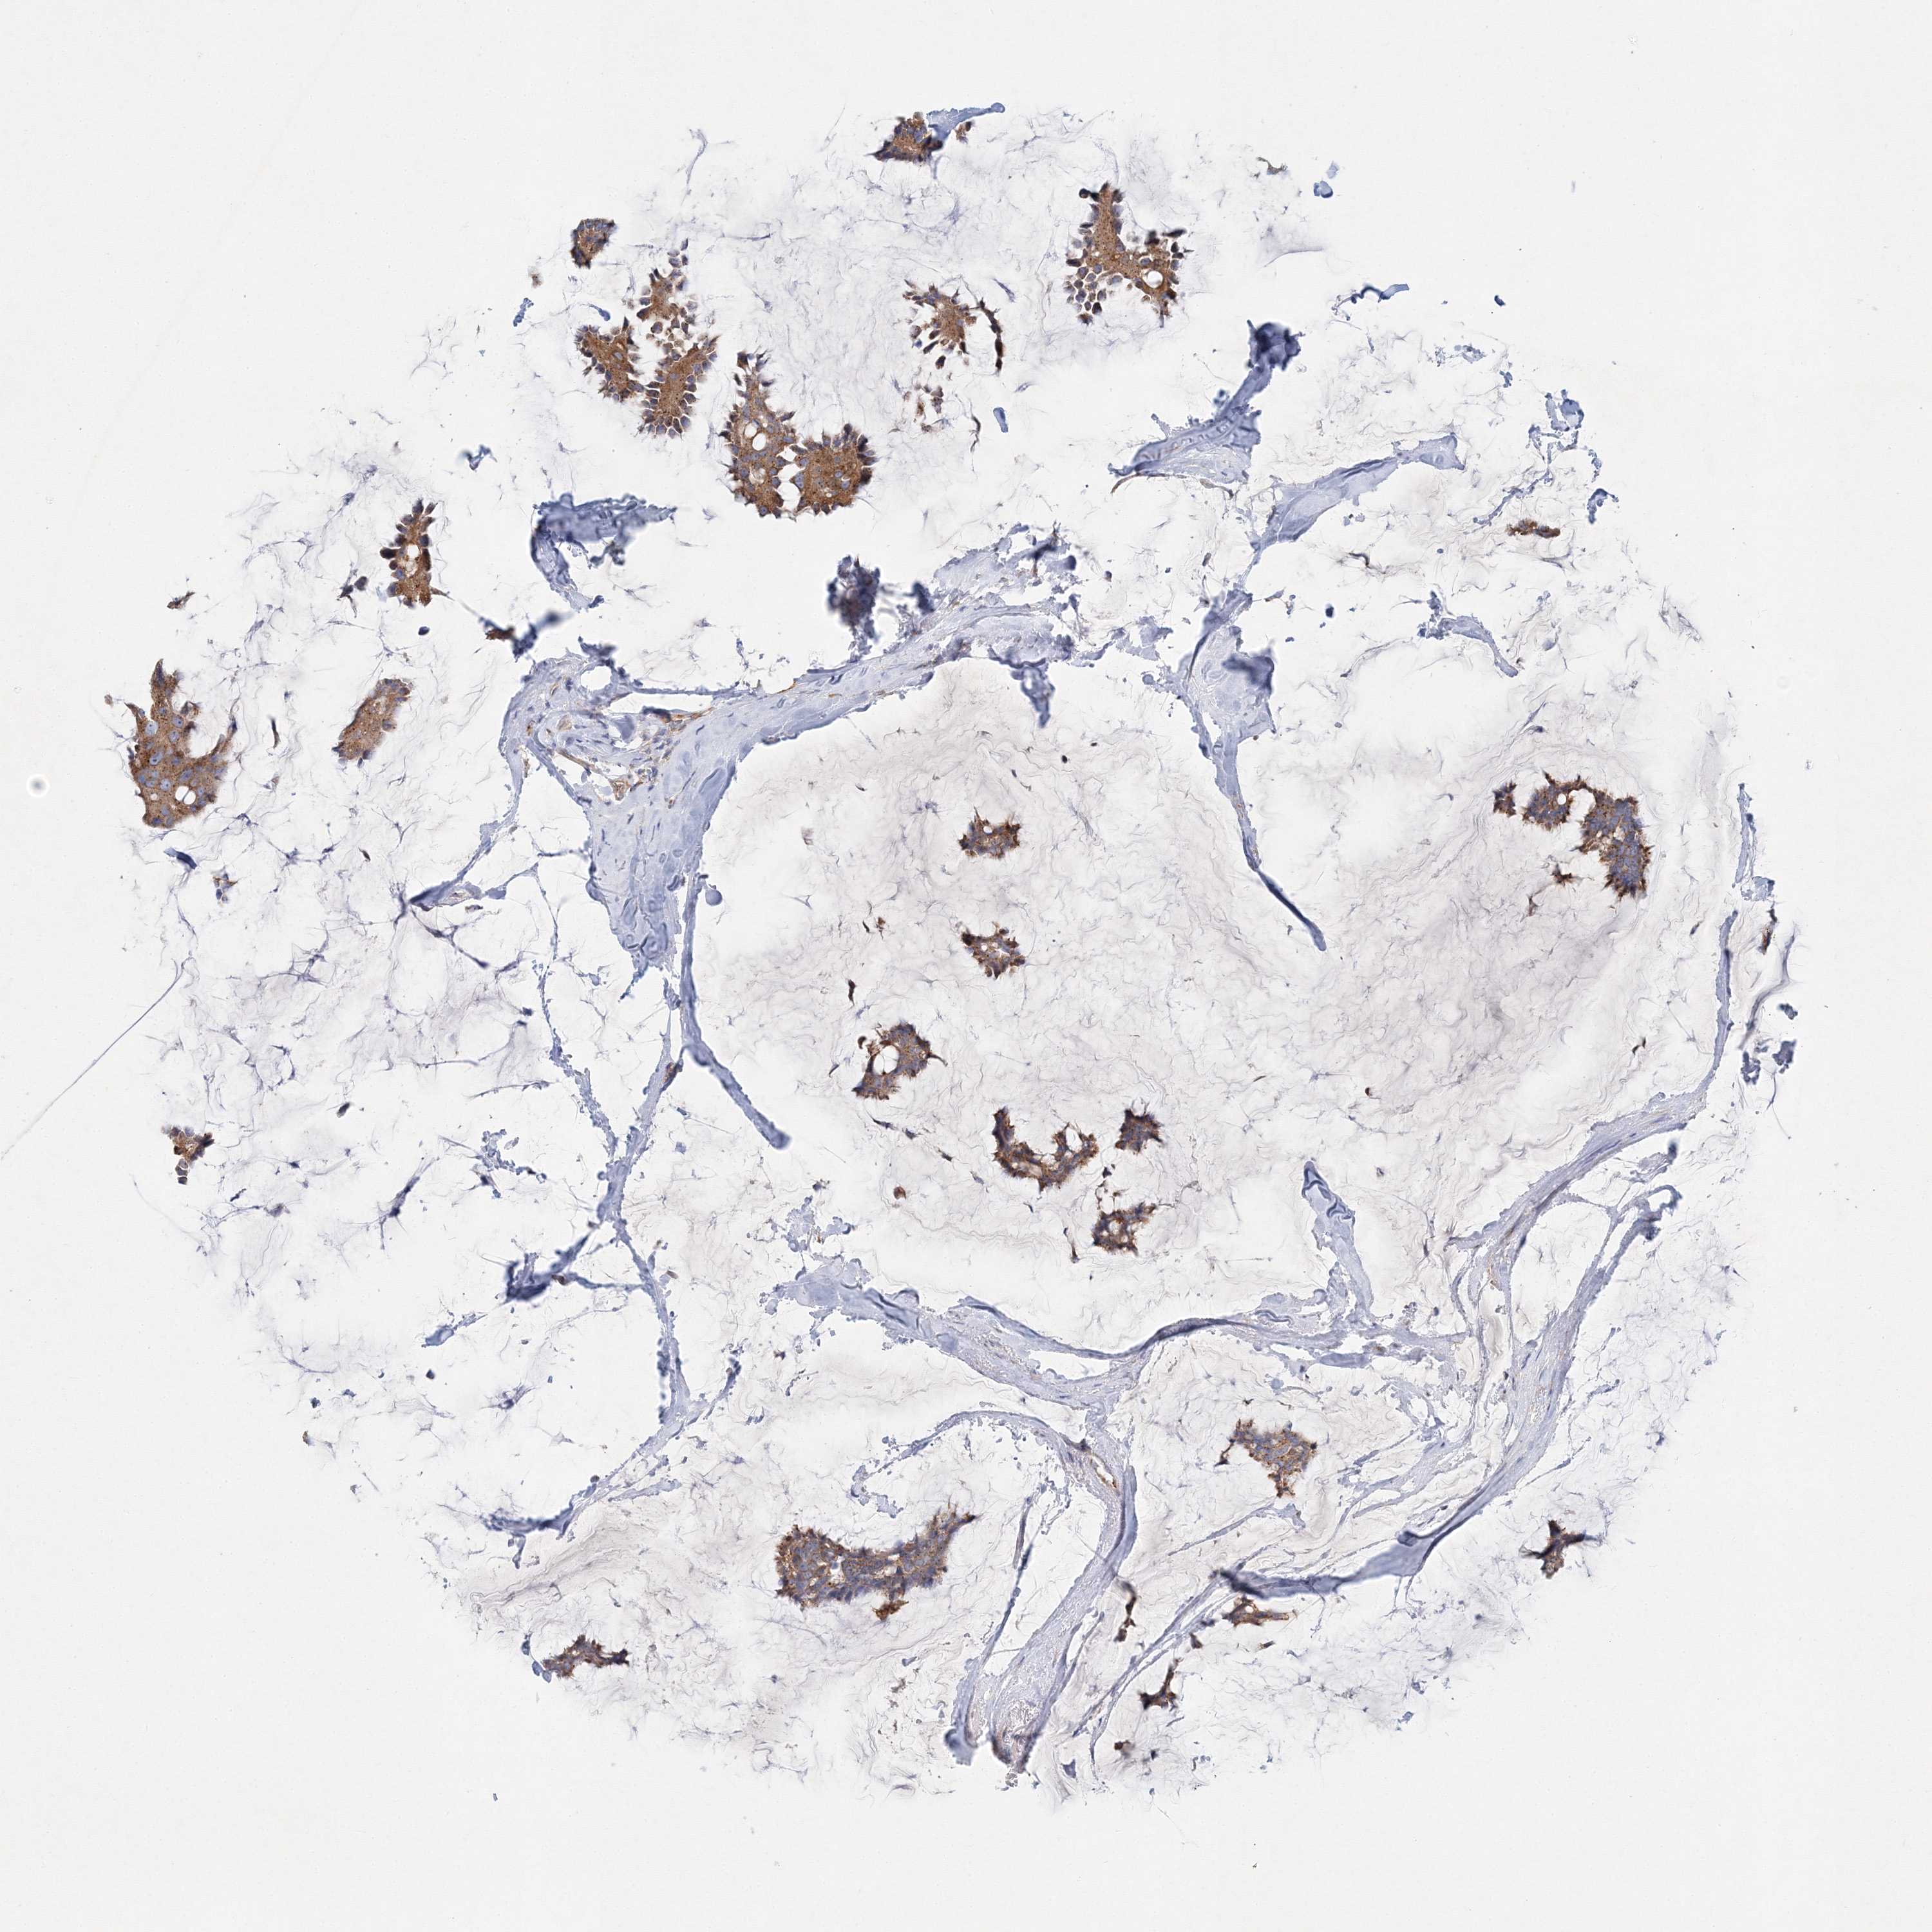

CANCER BREAST CANCER Show tissue menu

BRCA TCGA BRCA VALIDATION PROTEIN EXPRESSION